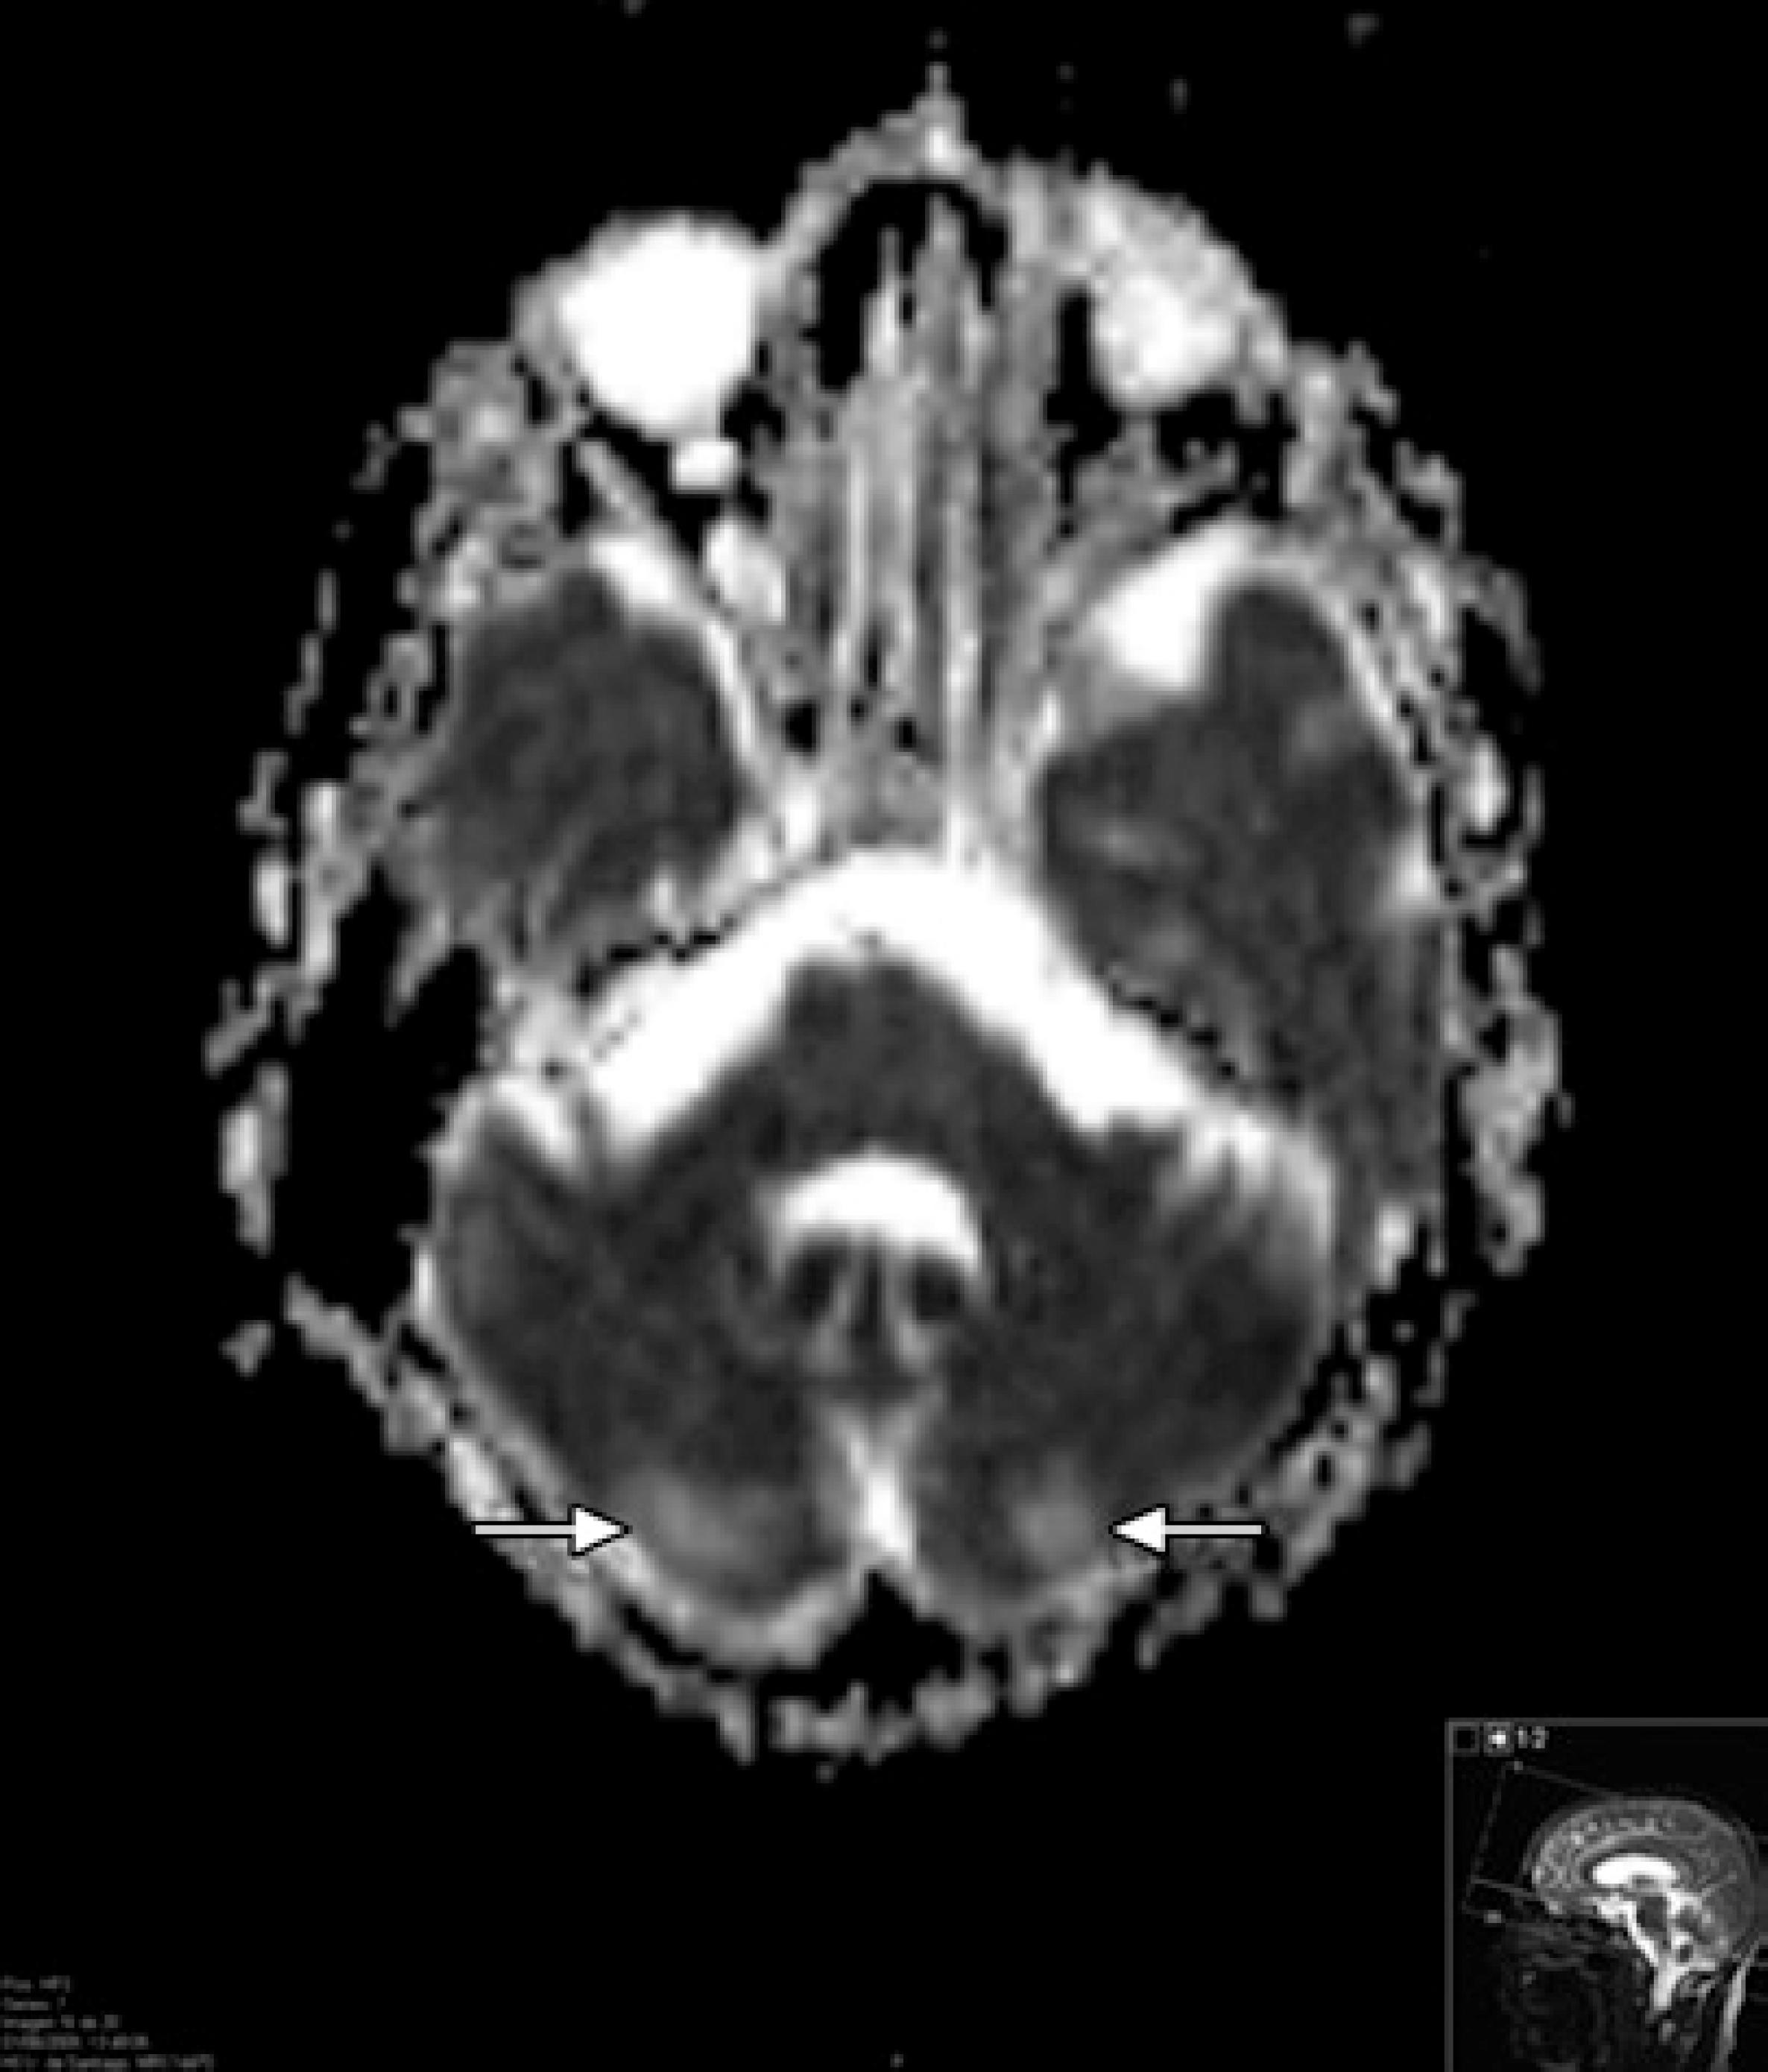

Posterior reversible encephalopathy syndrome is best managed by monitoring and treatment in the setting of a neurointensive care unit. Posterior reversible encephalopathy syndrome PRES is a clinical-neuroradiological entity characterized by headache vomiting altered mental status blurred vision and seizures as well as images suggesting white-gray matter edema involving in most cases posterior regions of the central nervous system as demonstrated by magnetic resonance image. The antepartum patient should be stabilized and then delivered.

Posterior reversible encephalopathy syndrome can be observed in patients with systemic lupus erythematosus and intensive care unit treatment may be required. Shortly after the description in 1996 two other case-series were published. Posterior reversible encephalopathy syndrome is a rare clinicoradiological entity characterized by typical MRI findings located in the occipital and parietal lobes caused by subcortical vasogenic edema.

Posterior reversible encephalopathy syndrome is a rare clinicoradiological entity characterized by typical MRI findings located in the occipital and parietal lobes caused by subcortical vasogenic edema.